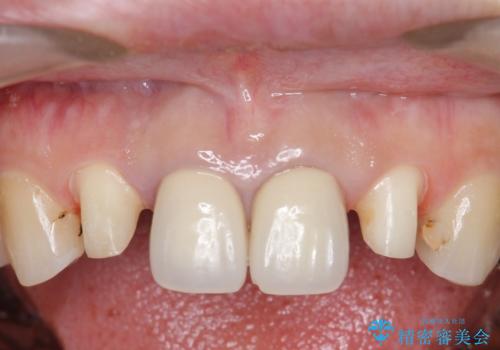

- 上顎の前から2番目の歯の古い樹脂をセラミックにしたいといらっしゃった方の症例です。

古い樹脂を除去後、オールセラミッククラウンによる補綴を行いました。